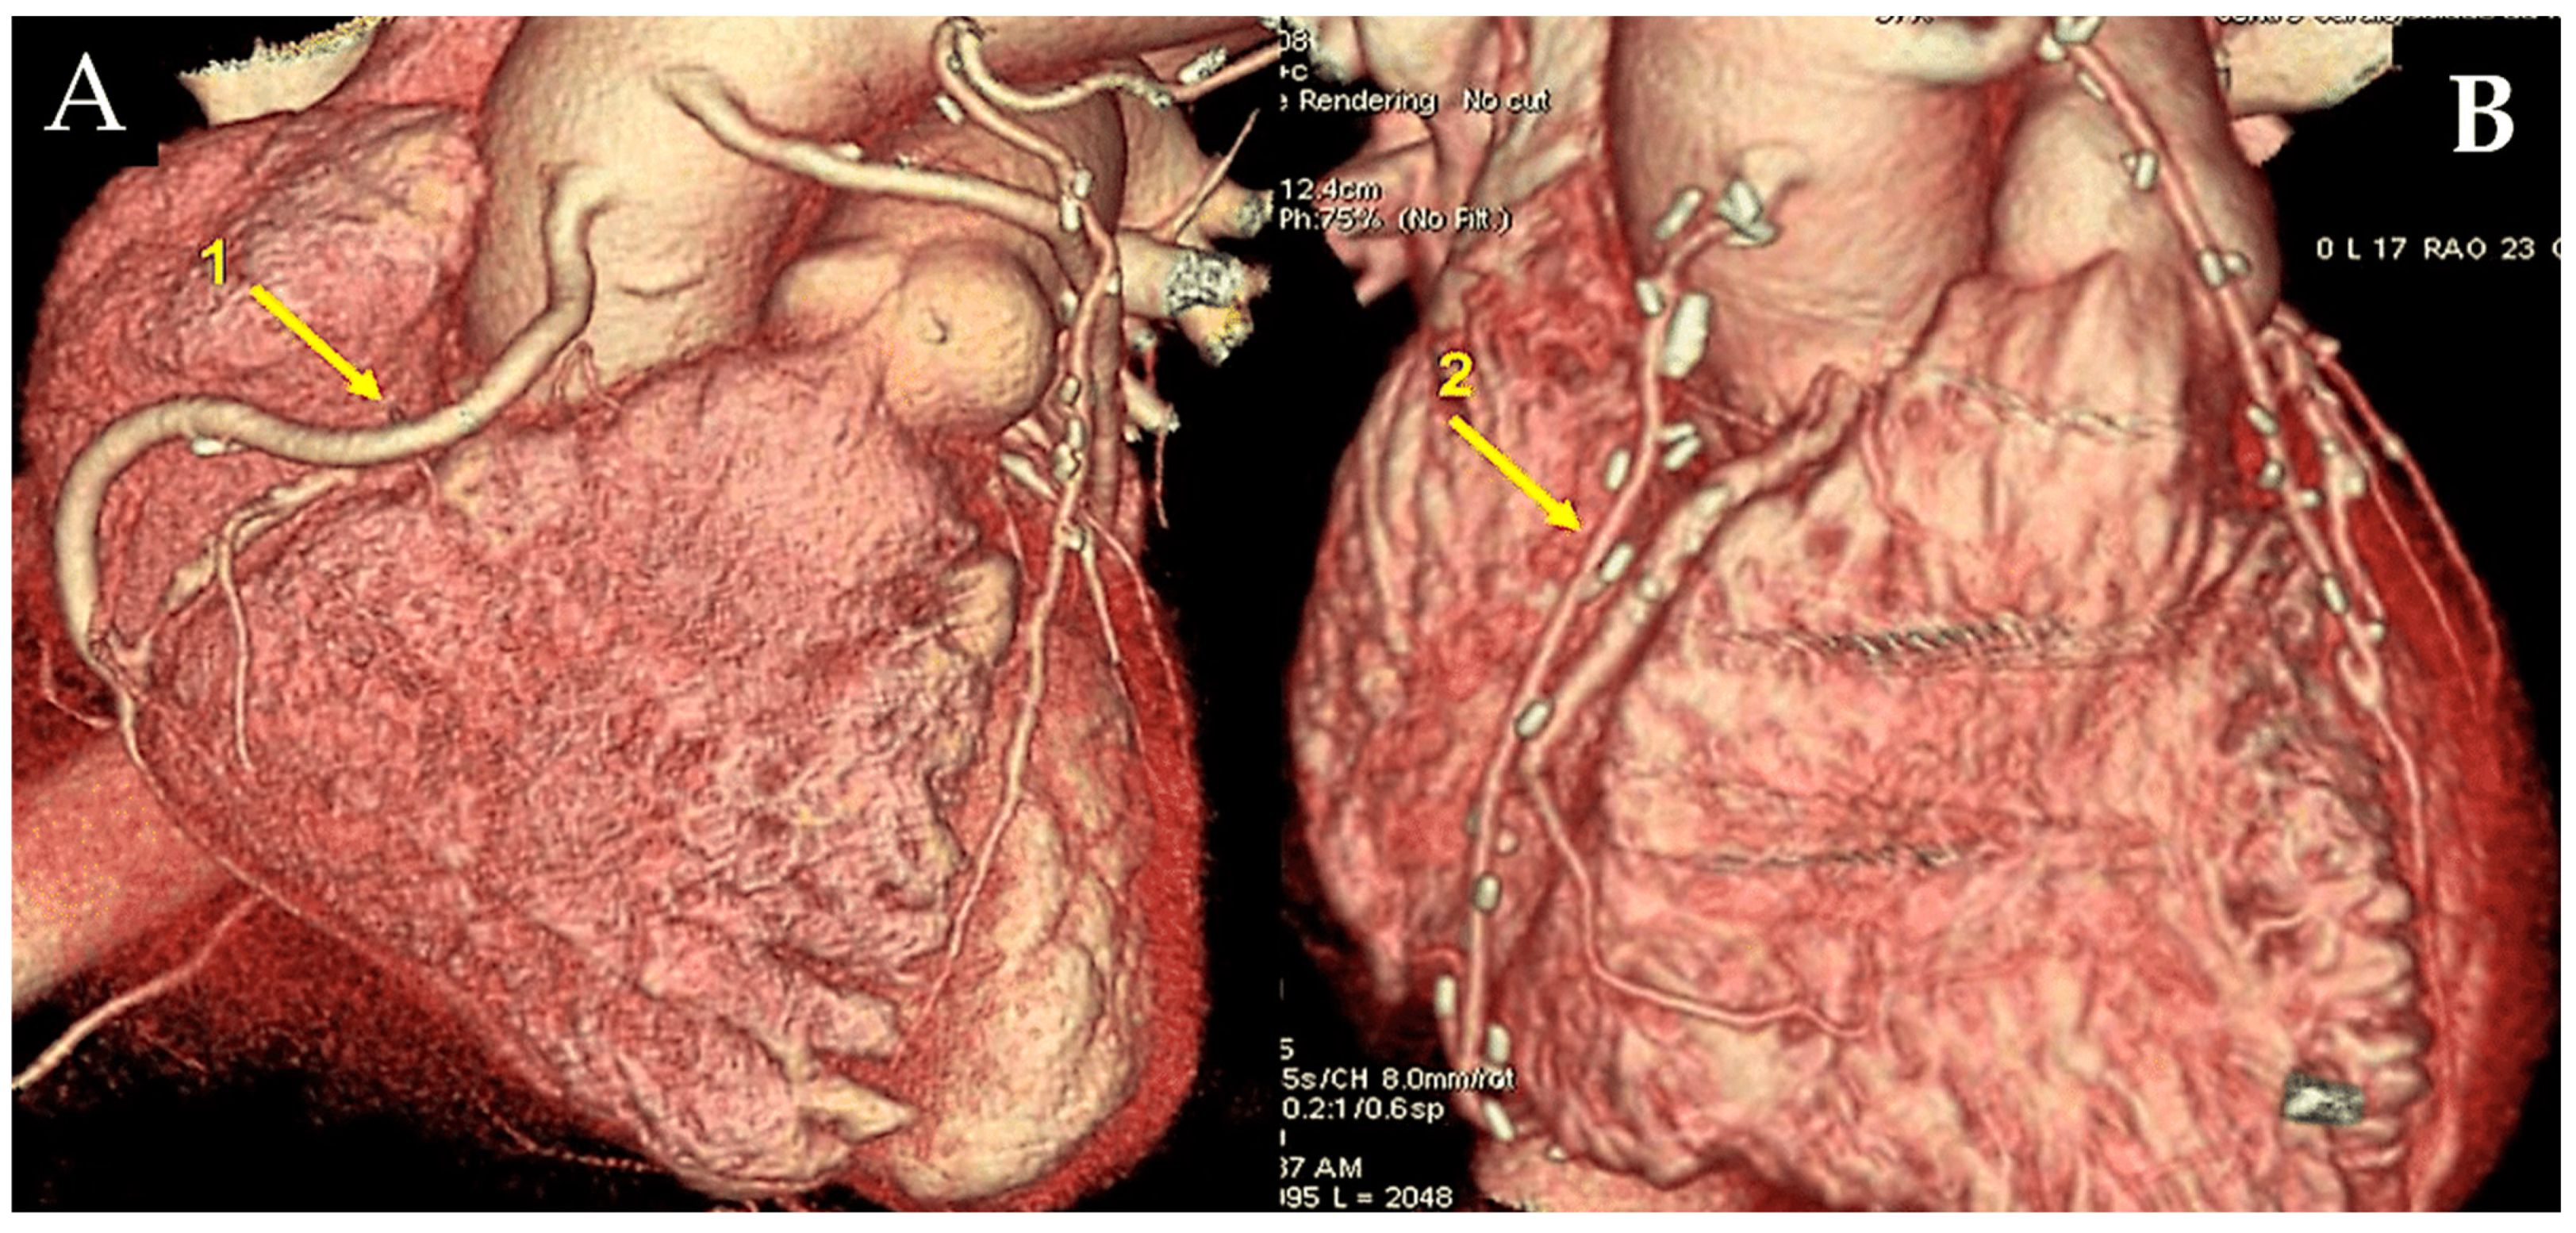

As a general principle, the surgeon advocates proximal anastomosis to the anterior portion of ascending aorta. Proximal anastomoses for individual conduits are achieved through the use of a suture to affix the graft end to side to an aortotomy in the proximal ascending aorta. A circular aperture measuring 3 mm in diameter is created in the aortic wall using a punch. The graft is then secured directly to the aorta using 7/0 Prolene sutures (Figure 1A,B).

Figure 1.

The illustration depicts a coronary artery bypass graft (CABG) procedure utilising radial artery (RA), saphenous vein grafts (SVGs), and left internal thoracic artery (LITA) (A,B). (A): The SVGs have been anastomosed to the posterior descending artery branch of the right coronary artery (1) and to the obtuse branch of the left coronary circumflex artery. The proximal anastomosis is secured on the ascending aorta (yellow arrow). The LITA has been anastomosed to the left anterior descending artery (LAD). (B): The RA (2) is anastomosed distally on the right coronary artery and proximally on the ascending aorta (yellow arrow), while the LITA is anastomosed on the LAD. Note that the venous graft size is greater than the arterial graft size.